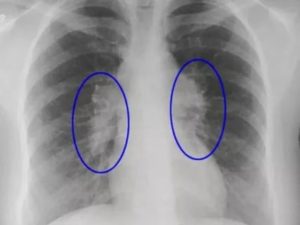

О тотальном затемнении и корнях легких на рентгене

к случаям затемнений относят замещения части легкого образованиями с плотной массой, вытесняющими воздух. это явление наблюдается при пневмониях, опухолевых новообразованиях, экссудативном плеврите. при полном затемнении легочного поля (2/3 и более его поверхности) диагностируют тотальное затемнение.

при расшифровке снимков усиленное внимание уделяется корням легких: рассыпчатым и магистральным. у первых развита сосудистая сеть, переходящая в тяжи, вторые представлены артерией легкого.

к признакам патологии относят усиление, уплотнение, тяжистость и расширенность корней.